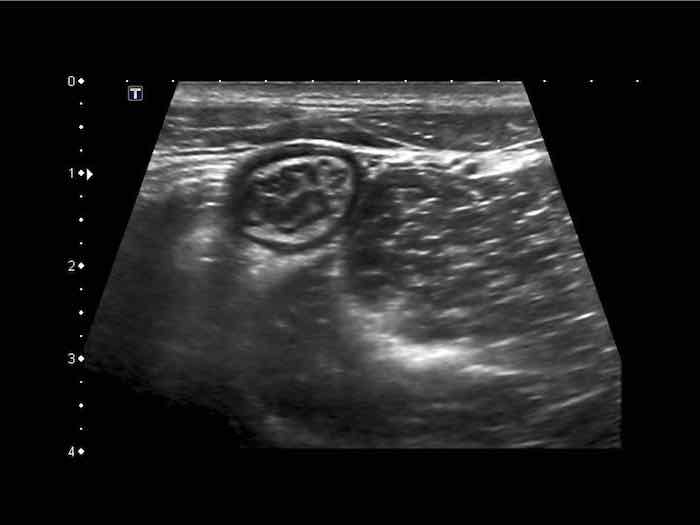

Đây là hình ảnh siêu âm của một trẻ 2 tuổi bị lồng ruột hồi manh tràng từng đợt, được khám trong khoảng thời gian giữa các cơn.

Hồi tràng với nhiều mảng Peyer sa vào manh tràng.

Hình ảnh siêu âm kinh điển của lồng ruột hồi-manh tràng ở hai trẻ khác nhau.

Trong cả hai trường hợp, đoạn hồi tràng bị lồng được định vị không đối xứng bên trong ống lồng ngoài, do mạc treo ruột tăng âm có chứa mỡ, bám vào hồi tràng và đi theo hồi tràng khi bị kéo vào trong.

Trong mạc treo, siêu âm cho thấy một hạch bạch huyết mạc treo (hbh) phóng đại ở cả hai.

Các hạch này phì đại như một phần của tình trạng tăng sản hạch bạch huyết toàn thân và khônghu trú trong lòng hồi tràng.

Do đó đây không phải là điểm dẫn đầu nguyên phát. Ở bệnh nhân bên phải, ruột thừa (mũi tên) cũng bị kéo vào trong.

Lưu ý cấu trúc đa lớp của thành bụng phía trước của phức hợp lồng ruột, đại diện cho ba lớp thành ruột bị gấp lại.